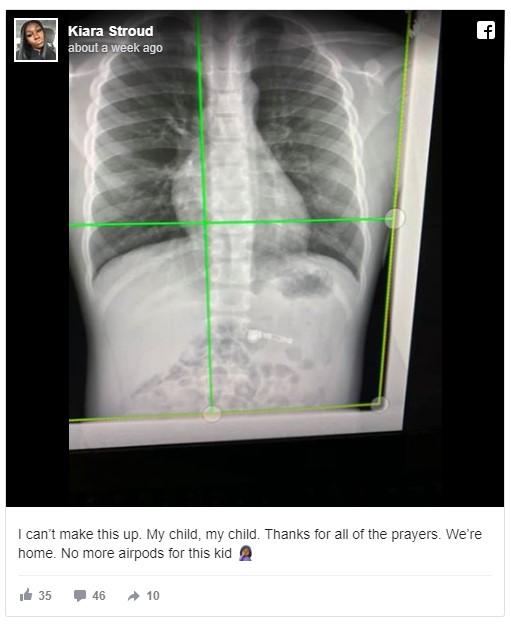

In a Facebook post, the boy’s mother, Kiara Stroud, shared an X-ray image that belongs to her son. The image clearly showed that there was a wireless earbud just below the rib cage. He was holding the stem of the earphone when he swallowed it.

Since the earphone had metal in it, it showed up in the X-ray image. The boy was admitted to an emergency room at the Children’s Healthcare of Atlanta. The doctors said that the Airpod will come out on its own. With this incident, parents really need to rethink if they ever want to get their 7-year-old kids a pair of Apple AirPods.